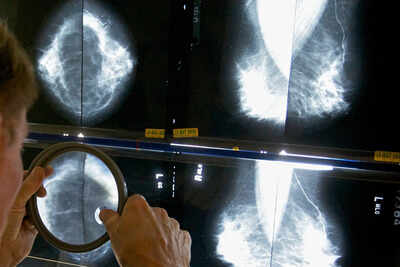

During the early years of the COVID-19 pandemic, experts worried that disruptions to cancer diagnosis and treatment would cost lives. A new study suggests they were right. The federally funded study published Thursday by the medical journal JAMA Oncology is being called the first to assess the effects of pandemic-related disruptions on the short-term survival of cancer patients. Researchers found that people diagnosed with cancer in 2020 and 2021 had worse short-term survival than those diagnosed between 2015 and 2019. That was true across a range of cancers, and whether they were diagnosed at a late or early stage. Of course, COVID-19 itself was especially dangerous to patients already weakened by cancer, but the researchers worked to filter out deaths mainly attributed to the coronavirus, so they could see if other factors played a role. The researchers were not able to definitively show what drove worse survival, said Todd Burus of the University of Kentucky, the study’s lead author. “But disruptions to the health care system were probably a key contributor,” said Burus, who specializes in medical data analysis. COVID-19 forced many people to postpone cancer screenings – colonoscopies, mammograms and lung scans – as the coronavirus overwhelmed doctors and hospitals, especially in 2020. Earlier research had shown that overall cancer death rates in the U.S. continued to decline throughout the pandemic, and there weren’t huge shifts in late diagnoses. Recinda Sherman, a researcher on that earlier paper, applauded the new work. “As this study is the first to document pandemic-related, cause-specific survival, I think it is important,” said Sherman, of the North American Association of Central Cancer Registries. “The more we understand about the impact of COVID-19, the better we will be able to prepare for the next one.” How could overall cancer death rates decline in 2020 and 2021, while short-term survival worsen for newly diagnosed patients? Cancer prevention, diagnosis and treatment measures that for years had been pushing cancer death rates down did not suddenly disappear during the pandemic, Burus noted. “We didn’t forget how to do those things,” he said. “But disruptions could have changed access, could have changed how quickly people were getting treated.” Further research will show if any impact was lasting, said Hyuna Sung, senior principal scientist and cancer epidemiologist at the American Cancer Society. “Transient declines in survival that quickly recover may have little impact on long-term mortality trends,” she said. The new study tapped national cancer registry data to focus more specifically on patients who had a first diagnosis of a malignant cancer in 2020 and 2021. More than 1 million people were diagnosed with cancer in those two years, and about 144,000 died within one year, according to the researchers’ data. The researchers looked at one-year survival rates for those patients, checking for what stage they were at the time of diagnosis. They calculated that one-year survival was lower for both early- and late-stage diagnoses, for all cancer sites combined. Most worrisome were large differences seen in colorectal, prostate and pancreatic cancers, they said.